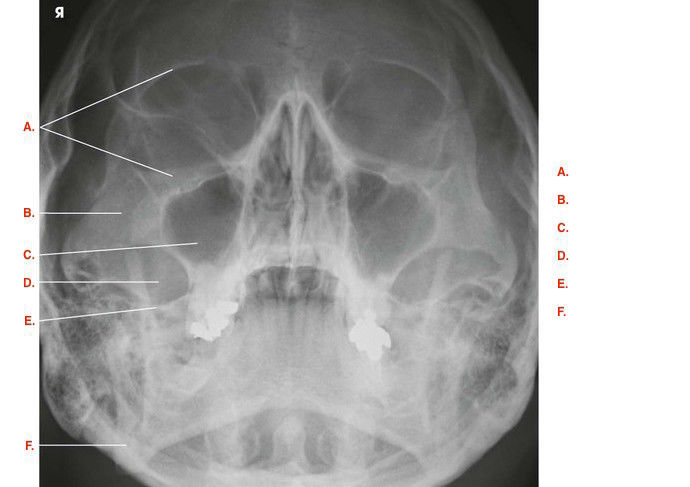

Question 3

Question

Label the image

Image:

f58fbf05-38aa-4e09-be15-7432d498314c (image/jpeg)

Answer

inferior orbital margin

maxillary sinus

zygomatic bone

petrous ridge

nasal septum

mandible